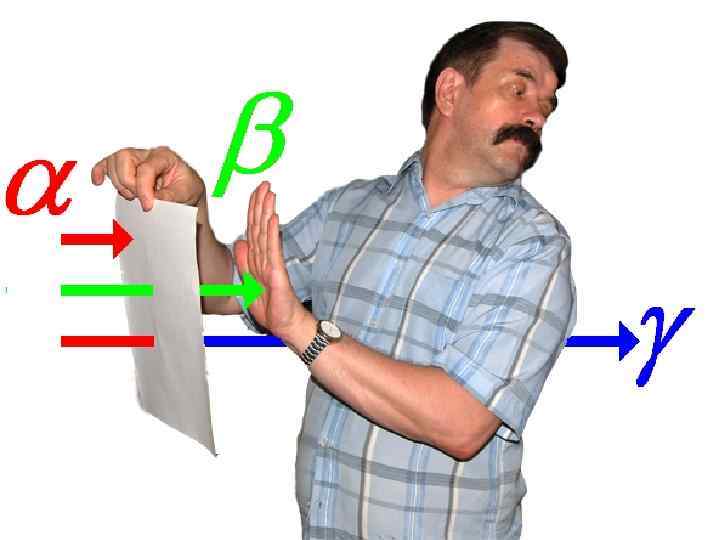

Основные требования к радиофармпрепаратам 3. Оптимальный спектр излучения * * 60 -80 Кэ. В 8 * ** * 120 -160 Кэ. В > 300 Кэ. В

Основные требования к радиофармпрепаратам 3. Оптимальный спектр излучения * * 60 -80 Кэ. В 8 * ** * 120 -160 Кэ. В > 300 Кэ. В